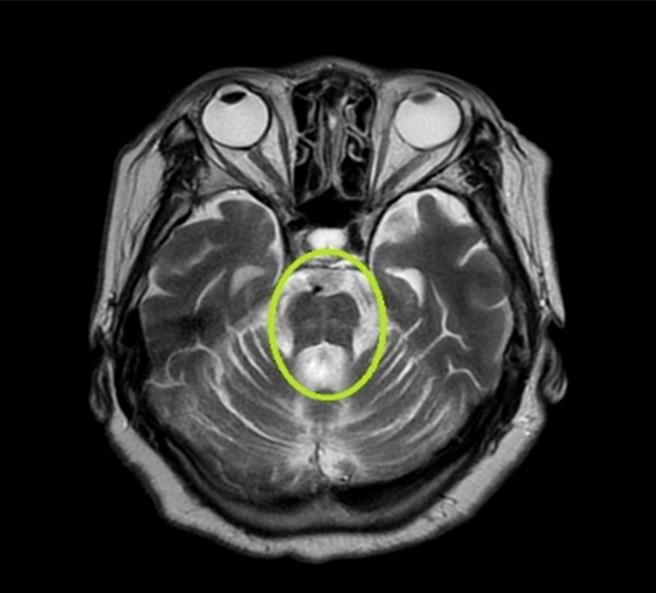

台中71岁黄阿嬷偶有时间感混乱、行走缓慢前兆,家人不以为意,但黄阿嬷近来对外界刺激没有反应甚至晕厥送急诊,才发现脑部核磁共振影像出现「热十字麵包徵候」,罹患罕见「多发性系统萎缩症」。(亚大医院提供/潘虹恩台中传真)

此外,黄阿嬷的脑部核磁共振影像也发现脑干异常萎缩与出现独特的「热十字麵包徵候」,才怀疑罹患「多发性系统萎缩症」。经多补充水分、饮食增加盐分摄取和穿高腰的弹性袜等非药物治疗后,症状明显改善顺利出院,但也提醒家属务必多关心黄阿嬷日常生活。